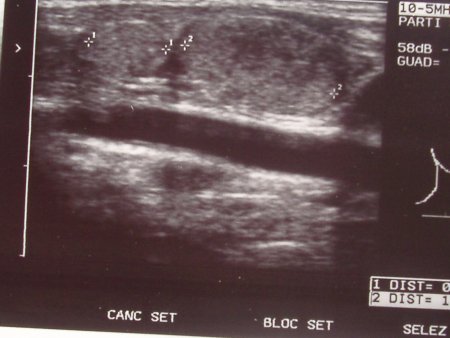

Nel sospetto di una linfoadenopatia reattiva ad una flogosi delle alte vie, dopo aver eseguito un tampone faringeo risultato negativo per SBEA, inizia, in maniera empirica, terapia antibiotica con cefalosporina orale che assume per 10 giorni senza risposta sul quadro clinico. Una nuova valutazione clinica conferma la già nota linfoadenopatia ed una attenta rivalutazione della tiroide evidenzia una modesta pastosità del lobo sin.. Esegue esami ematochimici, compresi gli ormoni tiroidei e la ricerca di anticorpi per infezioni virali, che risultano nella norma. L'ecografia del collo e della tiroide evidenzia un lobo tiroideo sin. quasi interamente occupato da un'estesa formazione di circa 21 mm di diametro (Figura 1 e Figura 2), a profili arrotondati e sfumati, ad ecostruttura solida iperriflettente ed irregolarmente vascolarizzata e la presenza di un linfonodo in sede istmica di circa 8 mm di diametro ed uno in sede laterocervicale sin. di circa 20 mm entrambi ad ecostruttura analoga a quella della formazione presente nel lobo tiroideo di sin.. Esegue agoaspirato con ago sottile che conferma il sospetto diagnostico di neoplasia maligna (CPT).

Figura 1